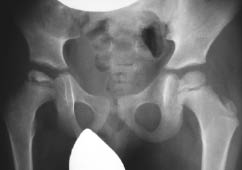

The pathogenesis of Perthes disease has not yet been fully studied. It is gratifying that over the past decade, there have been more and more scientific studies devoted to the pathogenesis of Perthes disease since the key to the success of adequate treatment of such complex orthopedic pathology is elucidating the mechanism of osteonecrosis. Some authors believe that the disorder (delay) of endostosis combined with the constitutional predisposition toward growth retardation leads to a decrease in the mechanical strength of the femoral head in patients with Perthes disease [1–4]. The disease is associated with improper differentiation of bone tissue by the controlling gene COL2A1. Its primary mutation triggers a cascade of pathological reactions that cause collagen formation disorder in the form of intratissual anomalies (markers of connective tissue dysplasia) in various organs, systems, and anatomical and topographical regions of an individual [5–7]. Osteonecrosis is caused by impaired intercellular interaction (osteoblast (osteocyte) – osteoclast) toward activation of osteoclasts [8]. Other researchers say that it occurs along with vascular pathology in boys with a hypersthenic constitution during a period of active growth. Lack of blood flow results in anemic infarct of the affected epiphysis of the femur [9–11]. Another possible scenario for the development of osteonecrosis is congenital maldevelopment of the spinal cord in the lumbar region (myelodysplasia). Disorder of the innervation of the hip joint (HJ) changes the size and number of vessels, as a result of which the blood flow in the HJ tissues is chronically reduced and the tissues are undernourished [12, 13]. At stage II of Perthes disease, the proximal epiphysis of the femur decreases in size, whereas at stage III, it is partially or completely subjected to resorption. At stage IV, the proximal epiphysis is partially restored. Subsequently, multiplanar deformities of the proximal femur are formed (Figures 1, 2).

Fig. 2. Radiograph of the hip joint in the anteroposterior projection of the patient T., 5 years. Diagnosis: "Perthes disease on the right, stage III. Total defeat of the proximal epiphysis of the right femur »